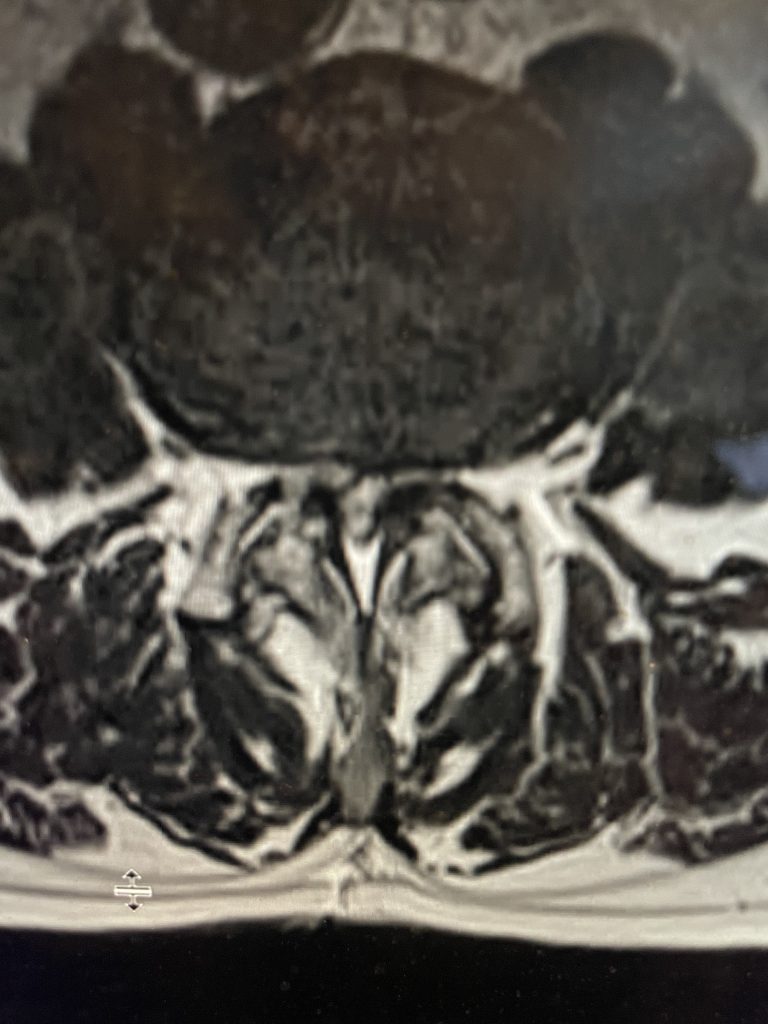

The spinal synovial cyst is one of the most interesting expressions of spinal instability. They emanate from the synovial lining of a degenerated facet joint that […]

The actual structural cause of lumbar thecal sac compression can vary in degenerative spondylolisthesis and stenosis. The culprits are commonly thickened ligamentum flavum or severe facet […]

People are obsessed with cysts! When you think about it, the body likes to form cysts. Why does this happen? Cysts can form just about anywhere […]